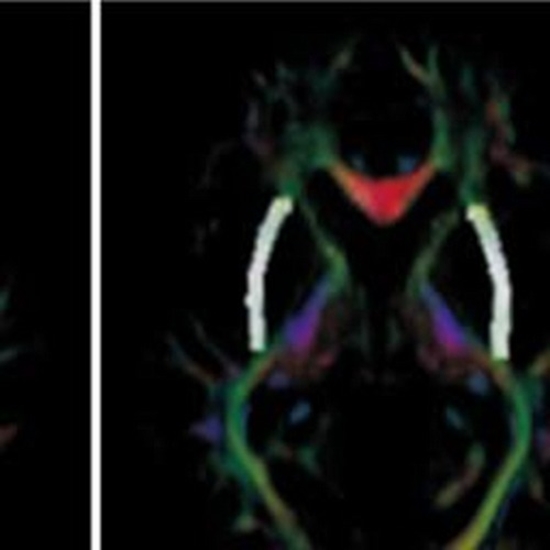

Posttraumatic stress disorder (PTSD) is a psychiatric condition that can develop after experiencing a traumatic event, and it is associated with a range of functional and structural brain abnormalities. This study aimed to investigate age-related differences in subcortical gray and white matter in veterans with PTSD. This study recruited 44 patients with PTSD and 48 healthy controls. Participants were divided into two age groups to evaluate structural magnetic resonance imaging analysis. The results showed that individuals with PTSD had significantly smaller subcortical gray matter volumes, including the bilateral thalamus, hippocampus, amygdala, left pallidum, and right accumbens-area (P<0.05). Diffusion tensor imaging analyses revealed lower fractional anisotropy in several white matter structures, including the anterior limb of the internal capsule, anterior corona radiata, and cingulum in both hemispheres (P<0.05). Additionally, the mean diffusivity was higher in the anterior limb of the internal capsule, anterior corona radiata and the right external capsule (P<0.05). A comparative analysis between two age groups, over 50 and under 50 years old, showed that younger PTSD patients had a reduction in volume and abnormality in the corresponding white matter in more regions compared to the control group. These findings suggest that PTSD is associated with significant structural alterations in the brain, which may contribute to the pathophysiology of the disorder. So, patient age is an effective factor in exposure to traumatic events and an older age is continuously associated with a worsening traumatic brain injury outcome